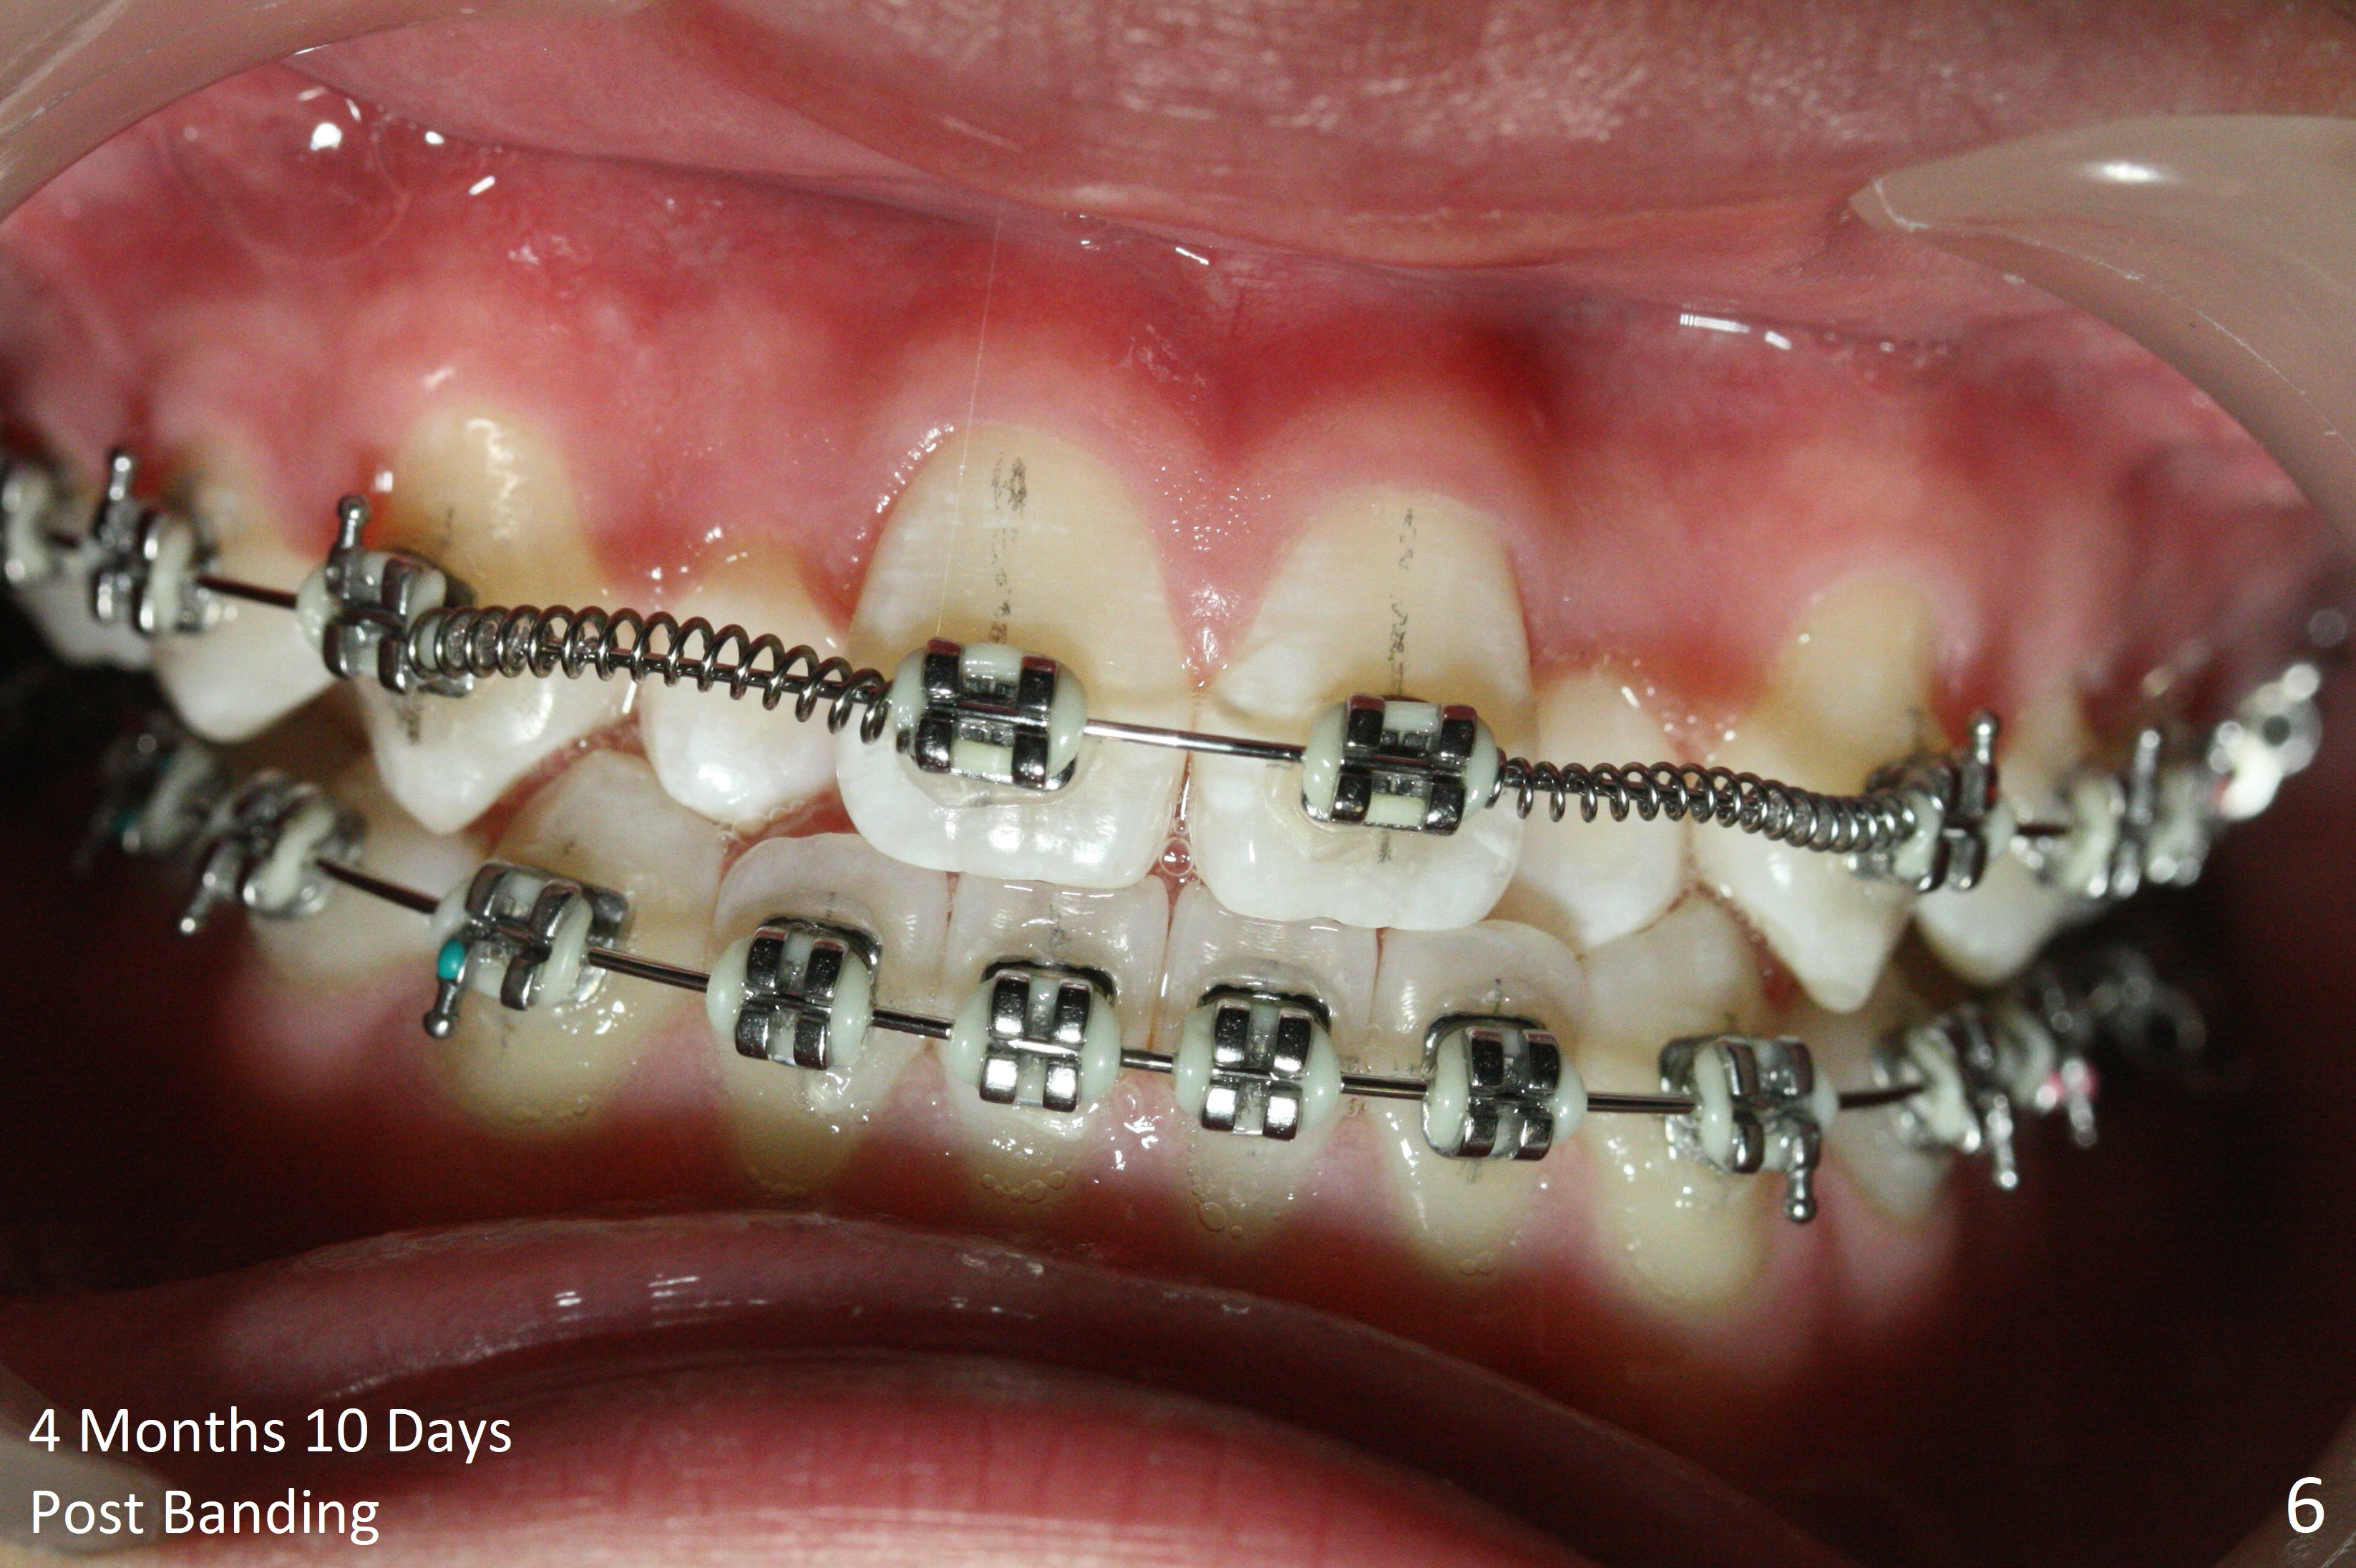

Cephalometric analysis shows Class III skeletal relationship. The roots of the upper anterior teeth (Fig.1,3 *) are prominent before treatment. In order to correct the cross bite of U2s (Fig.2,5), the upper arch needs expansion (Fig.4). Will the arch expansion cause buccal plate loss of the upper teeth? The upper dental midline matches the lower one by using the left open coil spring only (4 months 10 days post banding, Fig.6).